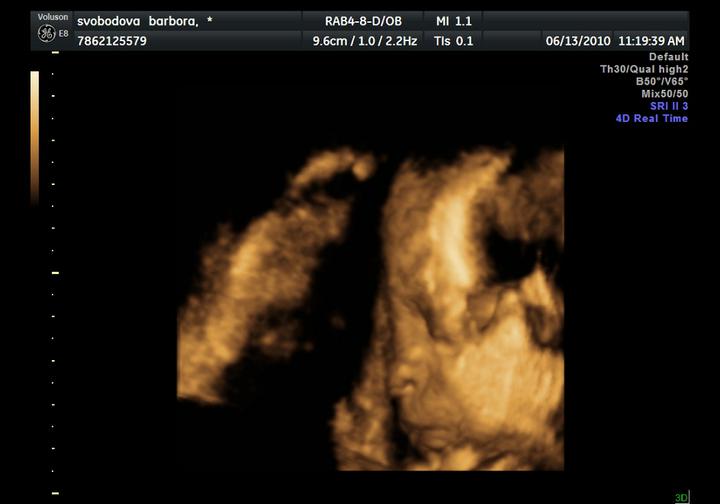

UZ byl naprosto úžasný zážitek, Adámek si cpal ručičky do pusinky, do nosánku, mrknul na nás, a ve finále ukázal fakáče 🙂

zítra jdeme na 3 D, už se nemůžem dočkat až broučka uvidíme